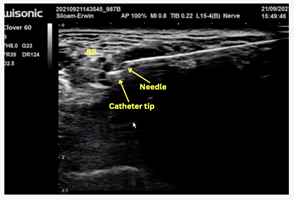

A Contiplex catheter was inserted through an interscalene approach into the right brachial plexus, and confirmed by deltoid muscle contraction upon nerve stimulation at 0.4 mA (Figure 2).

An initial bolus of 10 mL of 0.25% bupivacaine was administered, followed by connection of the catheter to a PCA pump containing 0.125% bupivacaine (100 mL). The infusion settings included a basal rate of 2 mL/hour, a bolus of 2 mL, a lockout interval of 20 minutes, and a maximum dose of 10 mg/hour. Continuous monitoring was performed for potential complications such as phrenic nerve palsy and Horner syndrome.

Figure 2: Placement of a CISB catheter tip using ultrasound